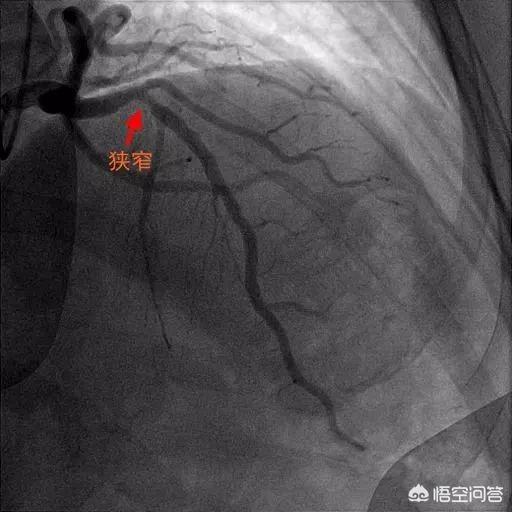

Comment la sténose est-elle calculée ?

En fait, une sténose de 75 % ou de 50 % n'est qu'une conclusion tirée par le médecin sur la base de son expérience et des multiples angles des résultats de l'imagerie, et techniquement il peut y avoir une petite erreur, par exemple, si je dis 70 % et qu'il dit 80 %, il n'y a rien de mal à cela.

La sténose de 75 % de ces deux vaisseaux n'est pas controversée :

La sténose critique fait l'objet d'une controverse. Nous devons donc forer à l'intérieur du vaisseau pour déterminer l'importance de cette sténose. La lésion est-elle stable ? Le vaisseau est-il vraiment ischémique ?

Il s'agit d'un test d'échographie intravasculaire, que nous avons tous pratiqué, et c'est la même chose : on obtient un petit ultrason, comme si on posait un stent, et on envoie cet ultrason vers la sténose du vaisseau, et en calculant le degré de sténose, en l'analysant pour découvrir la nature de la plaque, et en utilisant un ordinateur pour donner une indication sur l'existence ou non d'une ischémie dans le myocarde de ce vaisseau pathogène.

Si la sténose est effectivement grave et que l'ischémie est grave, nous posons un stent ; si la sténose n'est pas si grave, nous ne posons pas de stent pour l'instant ; de cette manière, c'est beaucoup plus objectif que de juger en conscience.

Le degré de sténose peut être mesuré par des instruments sans observation par l'œil humain.